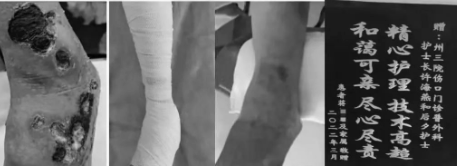

还有患者蒋某某,左下肢下肢静脉溃疡反复发作一年余,多处寻医未果,家属听说红河州第三人民医院伤口门诊能治疗各种慢性伤口,于是抱着“试试看”的心情,于2022年1月18日到伤口门诊就诊,采取压力疗法联合静脉溃疡敷料治疗下肢静脉溃疡,2个月后溃疡完全愈合,家属送来了感谢的锦旗,感叹到:“原来最好的医院就在我们身边,无需舍近求远到处寻医。”

此外,还有糖尿病患者普某某,因外伤导致右足感染,流脓形成窦道,常规换药1月余未见效果,医生风险告知,有可能截肢的风险,患者于2022年3月9日到伤口门诊就诊,焦虑万分,期望值很高,也给护理人员带来很大压力,伤口门诊护理团队通过学习糖尿病足全程管理知识,采用切开引流+新型敷料治疗糖足窦道,处理技术准确到位,3月29日,患者伤口完全愈合,:感激涕零:“非常感谢你们,保住了我的一只脚,我是家庭的顶梁柱,不能没有脚啊,真的很感谢!”